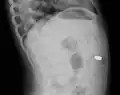

One of the most common locations for a foreign body is the alimentary tract.

It is possible for foreign bodies to enter the tract from the mouth or rectum.

Both children and adults experience problems caused by foreign objects becoming lodged within their bodies. Young children, in particular, are naturally curious and may intentionally put shiny objects, such as coins or button batteries, into their mouths. They also like to insert objects into their ear canals and nostrils.[1] The severity of a foreign body can range from unconcerning to a life-threatening emergency. For example, a coin causes local pressure on the tissue but generally is not a medical emergency to remove. A button battery, which can be a very similar size to a coin, generates hydroxide ions at the anode and causes a chemical burn in two hours.[2] An ingested button battery that is stuck in the esophagus is a medical emergency. In 2009, Avolio Luigi and Martucciello Giuseppe showed that although ingested nonmagnetic foreign bodies are likely to be passed spontaneously without consequence, ingested magnets (magnetic toys) may attract each other through children's intestinal walls and cause severe damage, such as pressure necrosis, perforation, intestinal fistulas, volvulus, and obstruction.[3]